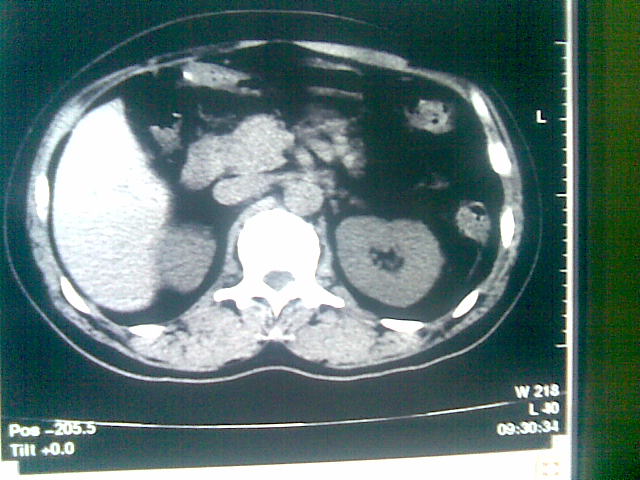

标题: CT23981:男,38岁阑尾炎术后透视胸腔积夜!做CT如下!积液包 [打印本页]

标题: CT23981:男,38岁阑尾炎术后透视胸腔积夜!做CT如下!积液包

可能与阑尾术后关系不太大,1.胸膜增厚粘连见少量气体。包裹脓气胸?左侧网膜囊脓肿?

少量积液部分粘连

左侧胸膜增厚、粘连+包裹液气胸。